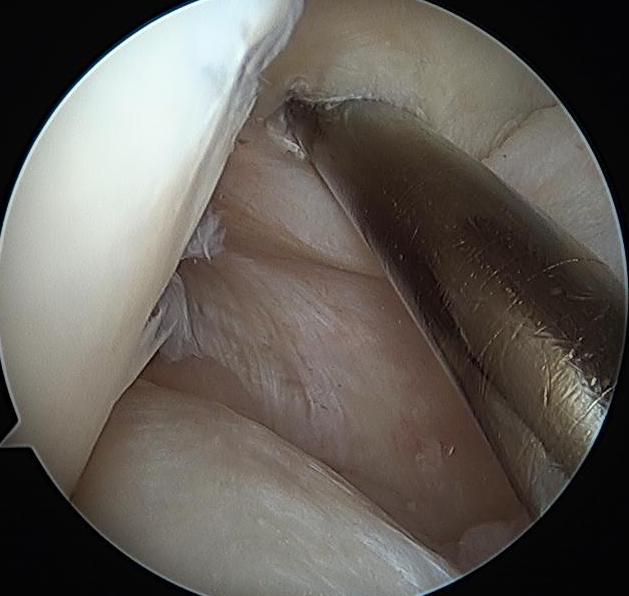

Femoral Tunnel

Femoral insertion is anterior

- 5 - 8 mm posterior to articular cartilage margin of medial femoral condyle

- 1 o'clock or 11 o'clock

- adjust position depending on using smaller HS or larger achilles tendon

- i.e. 7.5 mm tunnel for HS or 10 mm tunnel for achilles tendon

PCL femoral tunnels

PCL jig

- make medial dissection, subvastus plane

- drill beath pin outside in

- drill tunnel outside in or inside out (surgeon preference)

PCL femoral tunnel 1PCL femoral tunnel 2PCL femoral tunnel 3